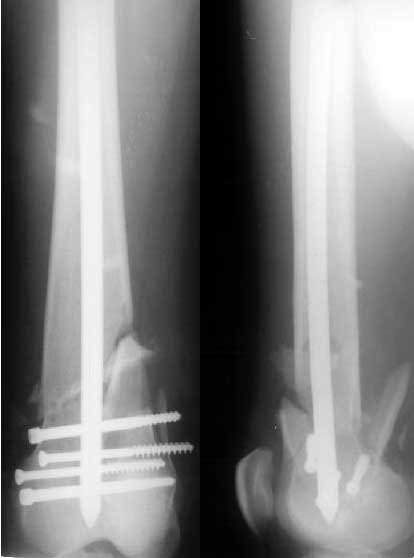

Пациент 27 лет оперирован 2.04.02 через 2 недели после открытого перелома дистального отдела бедренной кости (1 снимок).

Сделан антеградный закрытый интрамедуллярный остеосинтез UFN 11 мм (2 снимок). Вторая нога была ампутирована по месту первичного поступления. Для возможности ранней нагрузки использованы блокирующие винты 6 мм, для чего дистальные отверстия были рассверлены. К двум месяцам начал вставать на костыли, до того занимался разработкой движений в колене. Эти циклические движения в сочетании с тем, что зона концентрации нагрузок приходилась как раз на уровень отверстия, и что перелом открытый и тяжелый и не успел прочно схватиться, привели к перелому стержня 8 июня (3 снимок). Вчера госпитализировали. Такое осложнение у нас впервые. Пока думаем про реостесинтез - вытолкнуть дистальный отломок через дистально, да и через то же отверстие заштифтовать ретроградно. Илиналожить аппарат после удаления центрального отломка стержня, если что-то не будет получаться. Или подумать про пластинку?Заранее спасибо.

Если бы - есть заметная подвижность. Даже по снимку видно - отломки сдвинулись прилично, судя по положению частей стержня. Ну и при осмотре - качается...

Looking at the immediate postoperative xray, one would expect the fixation to fail since the fracture is very near the locking screw.(the nearest screw should be atleast 5 cm away from the fracture).It would have been better to do a retrograde nailing in the first instance to avoid this problem but now that it has happened the way to get out would be as you suggested by taking the nail pieces out and doing a retrograde nail with locking.Also the nail

looks too small for the size of the canal.